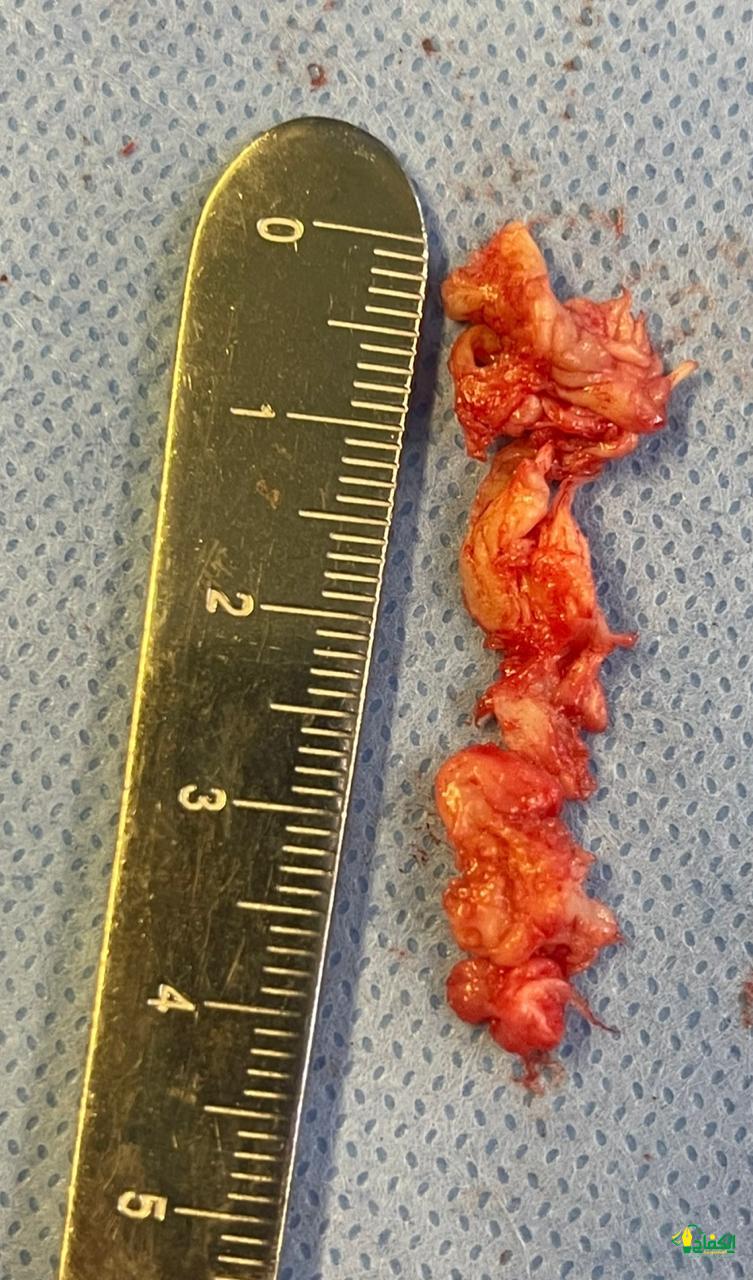

وبعد إجراء الفحوصات اللازمة، تبيّن وجود انزلاق غضروفي بين الفقرة القَطنية الخامسة والعَجُزية الأولى وقرر الفريق الطبي إجراء عملية جراحية بعد أن فشلت المسكنات والعلاج الطبيعي في النتائج المرجوة في تخفيف الألم، وبعد تنويم المريضة أُجريت لها عملية إزالة الغضروف الضاغط على الأعصاب باستخدام تقنية التدخل المحدود بالمنظار، عبر فتحة جراحية صغيرة لا تتجاوز 2 سم، وخرجت المريضة من المستشفى بعد يوم واحد من العملية وهي في حالة صحية جيدة.

يُذكر أن قسم جراحة المخ والأعصاب بمجمع الملك عبدالله الطبي بجدة يقوم بإجراء عمليات إزالة الغضروف بتقنية المنظار بشكل روتيني، مما يعكس التزام المجمع بتقديم أفضل الخدمات الطبية باستخدام أحدث التقنيات.